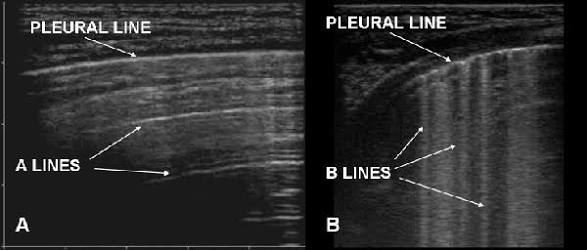

Method :-The transducer is oriented to scan between the ribs. The A lines and B lines are shown below:-

A lines:- A lines are horizontal lines that are brightly echogenic and located between the rib shadows when the probe is positioned longitudinally

B lines:- Pleural ultrasound image depicting B lines (“comet tail artifact”), which are seen in acute pulmonary edema and acute respiratory distress syndrome. The presence of B lines would provide an alternate explanation for increased density seen on the chest radiograph, other than pleural fluid.